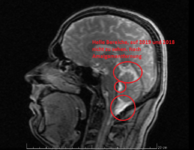

Weil ich Angst habe das mein Hirn von Schwermetalle geschädigt ist, und die Radiologie es nicht sieht ( weil die Microweiße Punkte im Hirn keiner Bedeutung zuweisen, diese sich aber über kurz oder Lang vergrößern können) habe ich die CD's der beiden MRT's aus den letzten beiden Jahren angefordert und möchte mittels Daunderers Bildmaterial mein Hirn mal vergleichen. Vielleicht erkenne ich ja Auffälligkeiten.

Um ein Microadenom auszuschließen erfolgt MRT 3 in den nächsten 4-8 Wochen. Dabei begleitet mich ein Neurologe der mir dann hoffentlich auch mal Diazepam verschreibt. Ich möchte das Zeug unbedingt testen und in wirklich schwierigen Zeiten so wie gestern und heute einfach mal 2 Tage nehmen um ne Pause von meinen Rückenproblemen zu haben. Plan sind 2-4 Einnahmezyklen pro Monat jeweils über 2 Tage um keine Abhängigkeit zu riskieren. Die Nebenwirkungen sind deutlich milder als bei Ortoton.